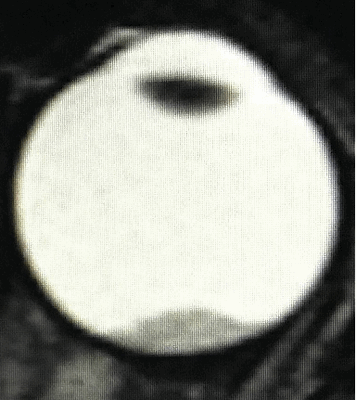

Рис. 3. Ретинобластома с эндофитным характером роста и опухолевыми клонами в стекловидном теле (А – до лечения, Б – после одного курса ИВХТ)

Во всех случаях отмечалась положительная динамика в виде частичной или полной регрессии опухолевых отсевов в стекловидное тело, уменьшения объема диссеминации опухолевых очагов по сетчатке (рис. 3).